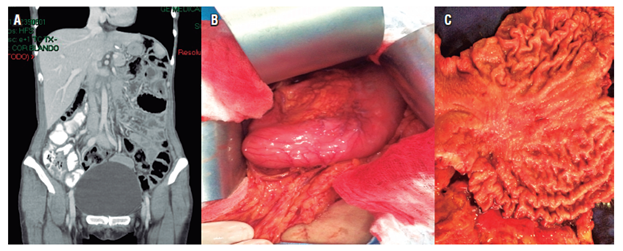

La paciente continuó con quimioterapia, con capecitabina y cisplatino. El día 16 de mayo, por decisión conjunta con la familia, se llevó a cirugía: se realizó la gastrectomía total con disección ganglionar D2. El resultado de patología fue el producto de gastrectomía total, adenocarcinoma gástrico de tipo difuso con células en anillo de sello, lesión de 6 x 5 cm, invasión tumoral hasta la grasa subserosa, invasión linfovascular y neural positivas, bordes proximal y distal libres de tumor, 5 de 17 ganglios positivos para compromiso tumoral, pT3pN2, epiplón negativo para tumor, rotulado diafragma izquierdo negativo para tumor, ganglios de la arteria hepática negativos para tumor, borde esofágico por aparte negativo para tumor y estado de HER2 negativo (Figura 3).

La paciente se remitió a oncología, donde se le ordenó 3 ciclos más de quimioterapia con cisplatino y capecitabina. En el último control en noviembre del 2016 resultó asintomática con marcadores tumorales elevados y un índice de Karnofsky del 100%. Un control tomográfico evidenció un compromiso ganglionar paraaórtico. Se reinició un nuevo esquema de quimioterapia con irinotecán (250 mg IV, día 1 y día 15).